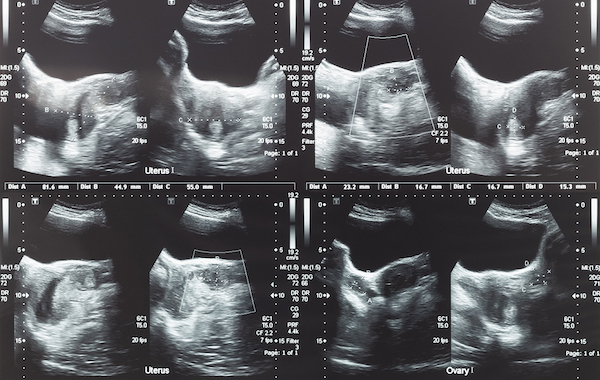

Në kuadër të Muajit të Gruas, United Hospital ka prezantuar një ofertë të veçantë për kujdesin ndaj shëndetit të grave, duke ofruar një pako gjinekologjike me çmim proporcional gjatë gjithë muajit mars.

Në këtë institucion shëndetësor, kujdesi për pacientët është gjithmonë prioritet. Departamenti i Gjinekologjisë dhe Obstetrisë në United Hospital ofron shërbime moderne diagnostikuese dhe trajtuese, të realizuara nga një ekip i përkushtuar dhe i kualifikuar mjekësh, duke përdorur teknologjinë më të avancuar për zbulimin dhe trajtimin e sëmundjeve gjinekologjike.

Për të inkurajuar kontrollet e rregullta dhe kujdesin ndaj shëndetit të gruas, gjatë muajit mars ofrohet një pako gjinekologjike me çmim promocional prej 50 euro, nga çmimi i rregullt prej 79 euro.

Pakoja përfshin:

- Echo gjinekologjike

- PAP Test

- Strisho vaginale

- Strisho cervikale

- Vizitë mjekësore

Kjo pako u mundëson grave të kryejnë një kontroll të plotë gjinekologjik, i cili është shumë i rëndësishëm për diagnostikimin e hershëm dhe parandalimin e problemeve shëndetësore.

Nëse keni nevojë për kontroll, këshillim profesional apo trajtim të avancuar, Departamenti i Gjinekologjisë dhe Obstetrisë në United Hospital ofron kujdes të specializuar dhe profesional për shëndetin e gruas.